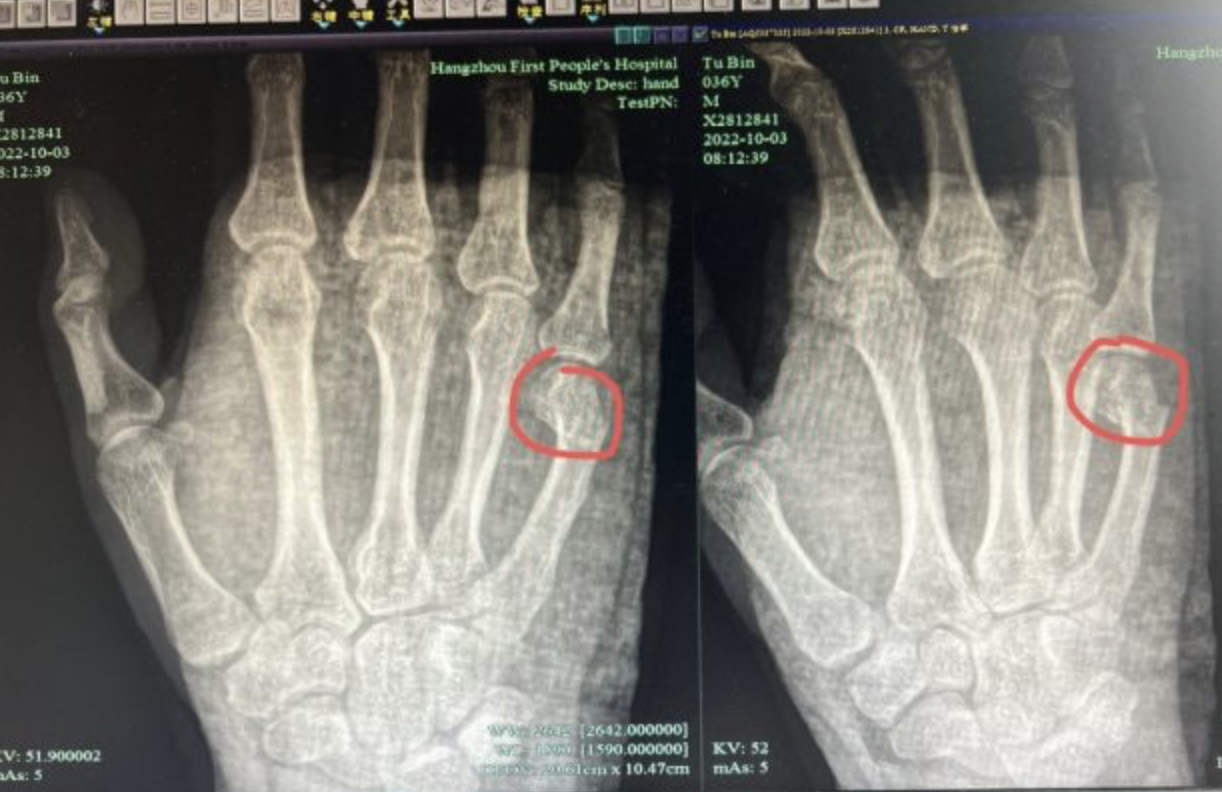

吳男原以為是用力過猛,過一下就好了,但手痛了一整天還是沒有好轉,反而還瘀青紅腫,於是由母親陪伴前往醫院就診。照X光後,發現吳男右手掌小指處骨折,且必須住院治療。吳男感嘆「這一拳要是打在孩子身上,麻煩就大了」。